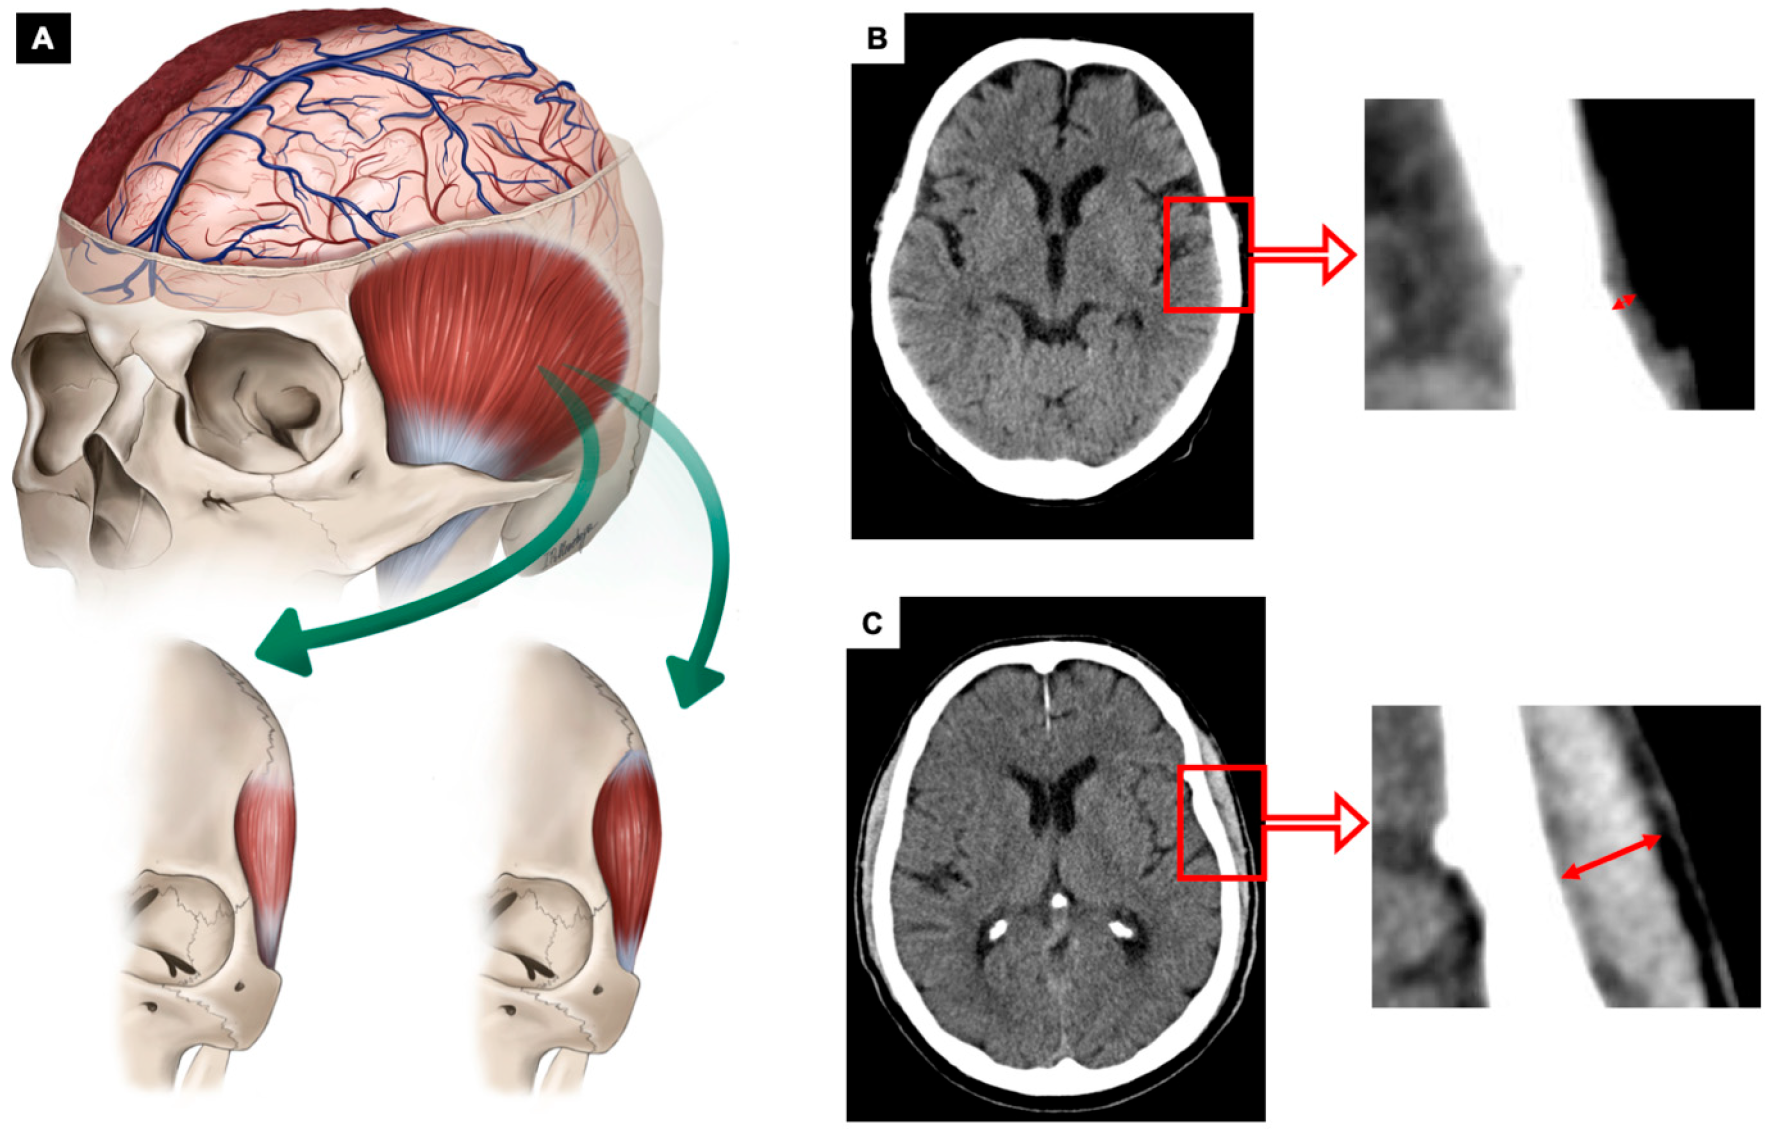

2.2. Image Analysis